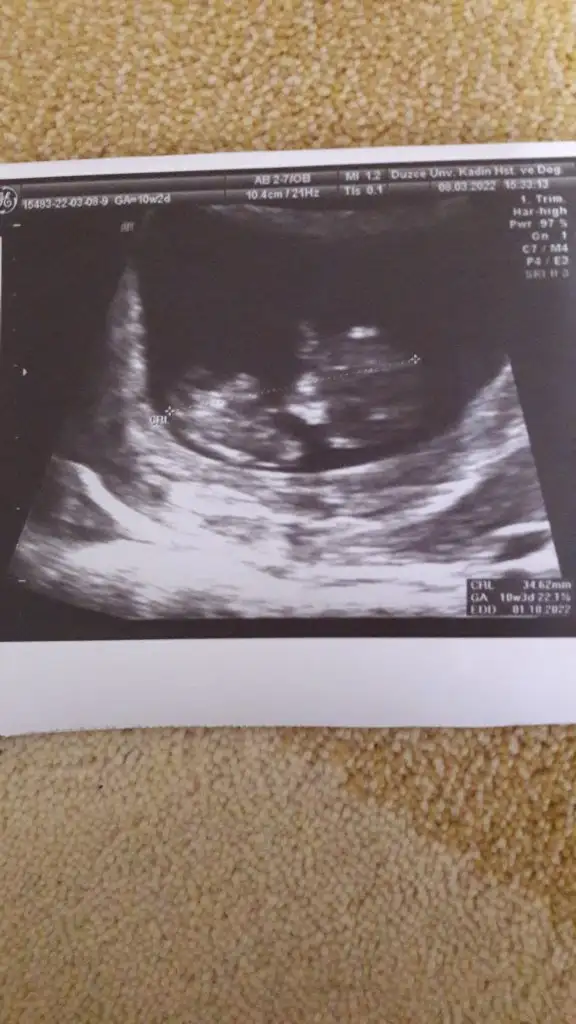

Bende yorum istiyorum lutfen

Eklentiler

• IMG-20220311-WA0012.webp

IMG-20220311-WA0012.webp

17,3 KB · Görüntüleme: 47